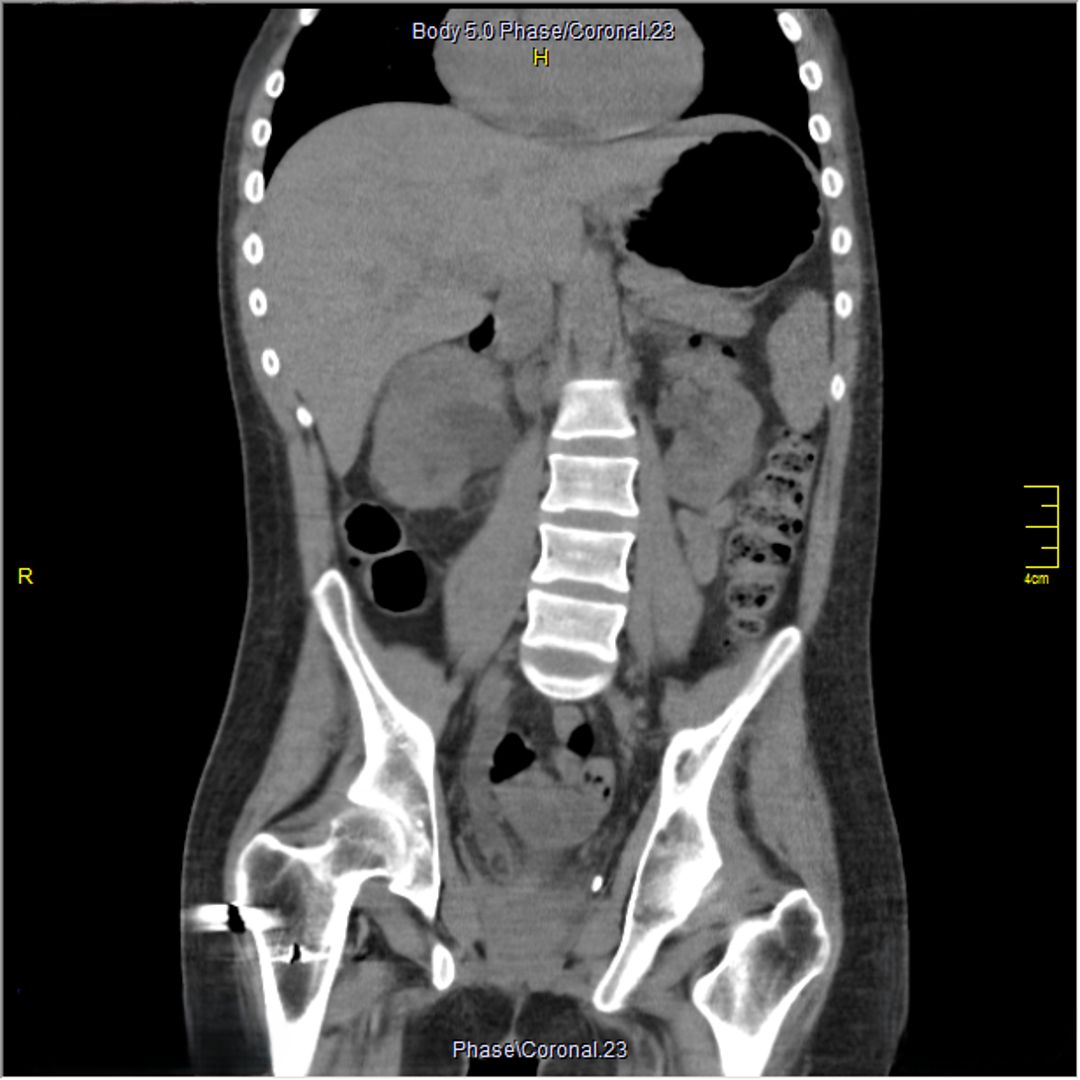

A 23-year-old male with a history of traumatic spinal cord injury (T3 ASIA A), iatrogenic urethral stenosis limiting clean intermittent catheterization (CIC), and low bladder capacity, was admitted for a planned open cystostomy and bladder stone extraction. Following stone removal, a 24-French SPC was placed. On postoperative day 3, the patient developed AD, characterized by hypertensive urgency and profuse sweating. Renal ultrasound revealed right-sided hydronephrosis. A CT scan confirmed SPC misplacement, with the catheter tip located inside the right distal ureter.

Figure 2 Coronal view of the SPC's tip in the distal right ureter provoking hydronephrosis